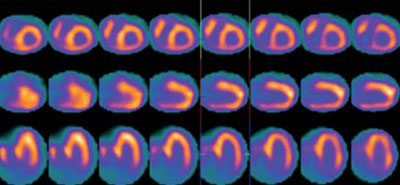

Se completa la evaluación con un centellograma con 99mTc-PYP, incluyendo imágenes planares y SPECT gatillado. Se demostró intensa captación difusa del radiotrazador en todo el miocardio, con grado 3 de Perugini (Figura 5) e índice H/CL de 1,84 (Figura 6). Las imágenes de SPECT evidenciaron, además, clara visualización del VD (Figura 7) y permitieron valorar la función ventricular, con resultados similares a los del estudio de perfusión miocárdica. Según la literatura, los hallazgos son patognomónicos de amiloidosis subtipo ATTR.

En este reporte de caso se presenta un paciente con ECO y RM sugestivos de amiloidosis y un estudio de perfusión miocárdica sin evidencia de isquemia. Se realiza un estudio con 99mTc-PYP compatible con amiloidosis subtipo ATTR. Debemos señalar que la diferencia de captación entre los dos subtipos (ATTR y AL) se debe a la mayor concentración de calcio en las fibras de amiloide en el subtipo ATTR, aunque en estadios tardíos del subtipo AL, la captación puede estar aumentada, en general sin llegar al grado 3 de Perugini. Los hallazgos dados por la técnica de MN, sumados al ECG, la RM y el eco Doppler tienen valor diagnóstico incremental, siendo el centellograma con 99mTc-difosfonatos el método que permite identificar mejor el subtipo de amiloide de forma no invasiva10,11. La limitación del caso actual es que no se cuenta con histopatología para certificar el diagnóstico, ya que no fue realizada la biopsia cardíaca.